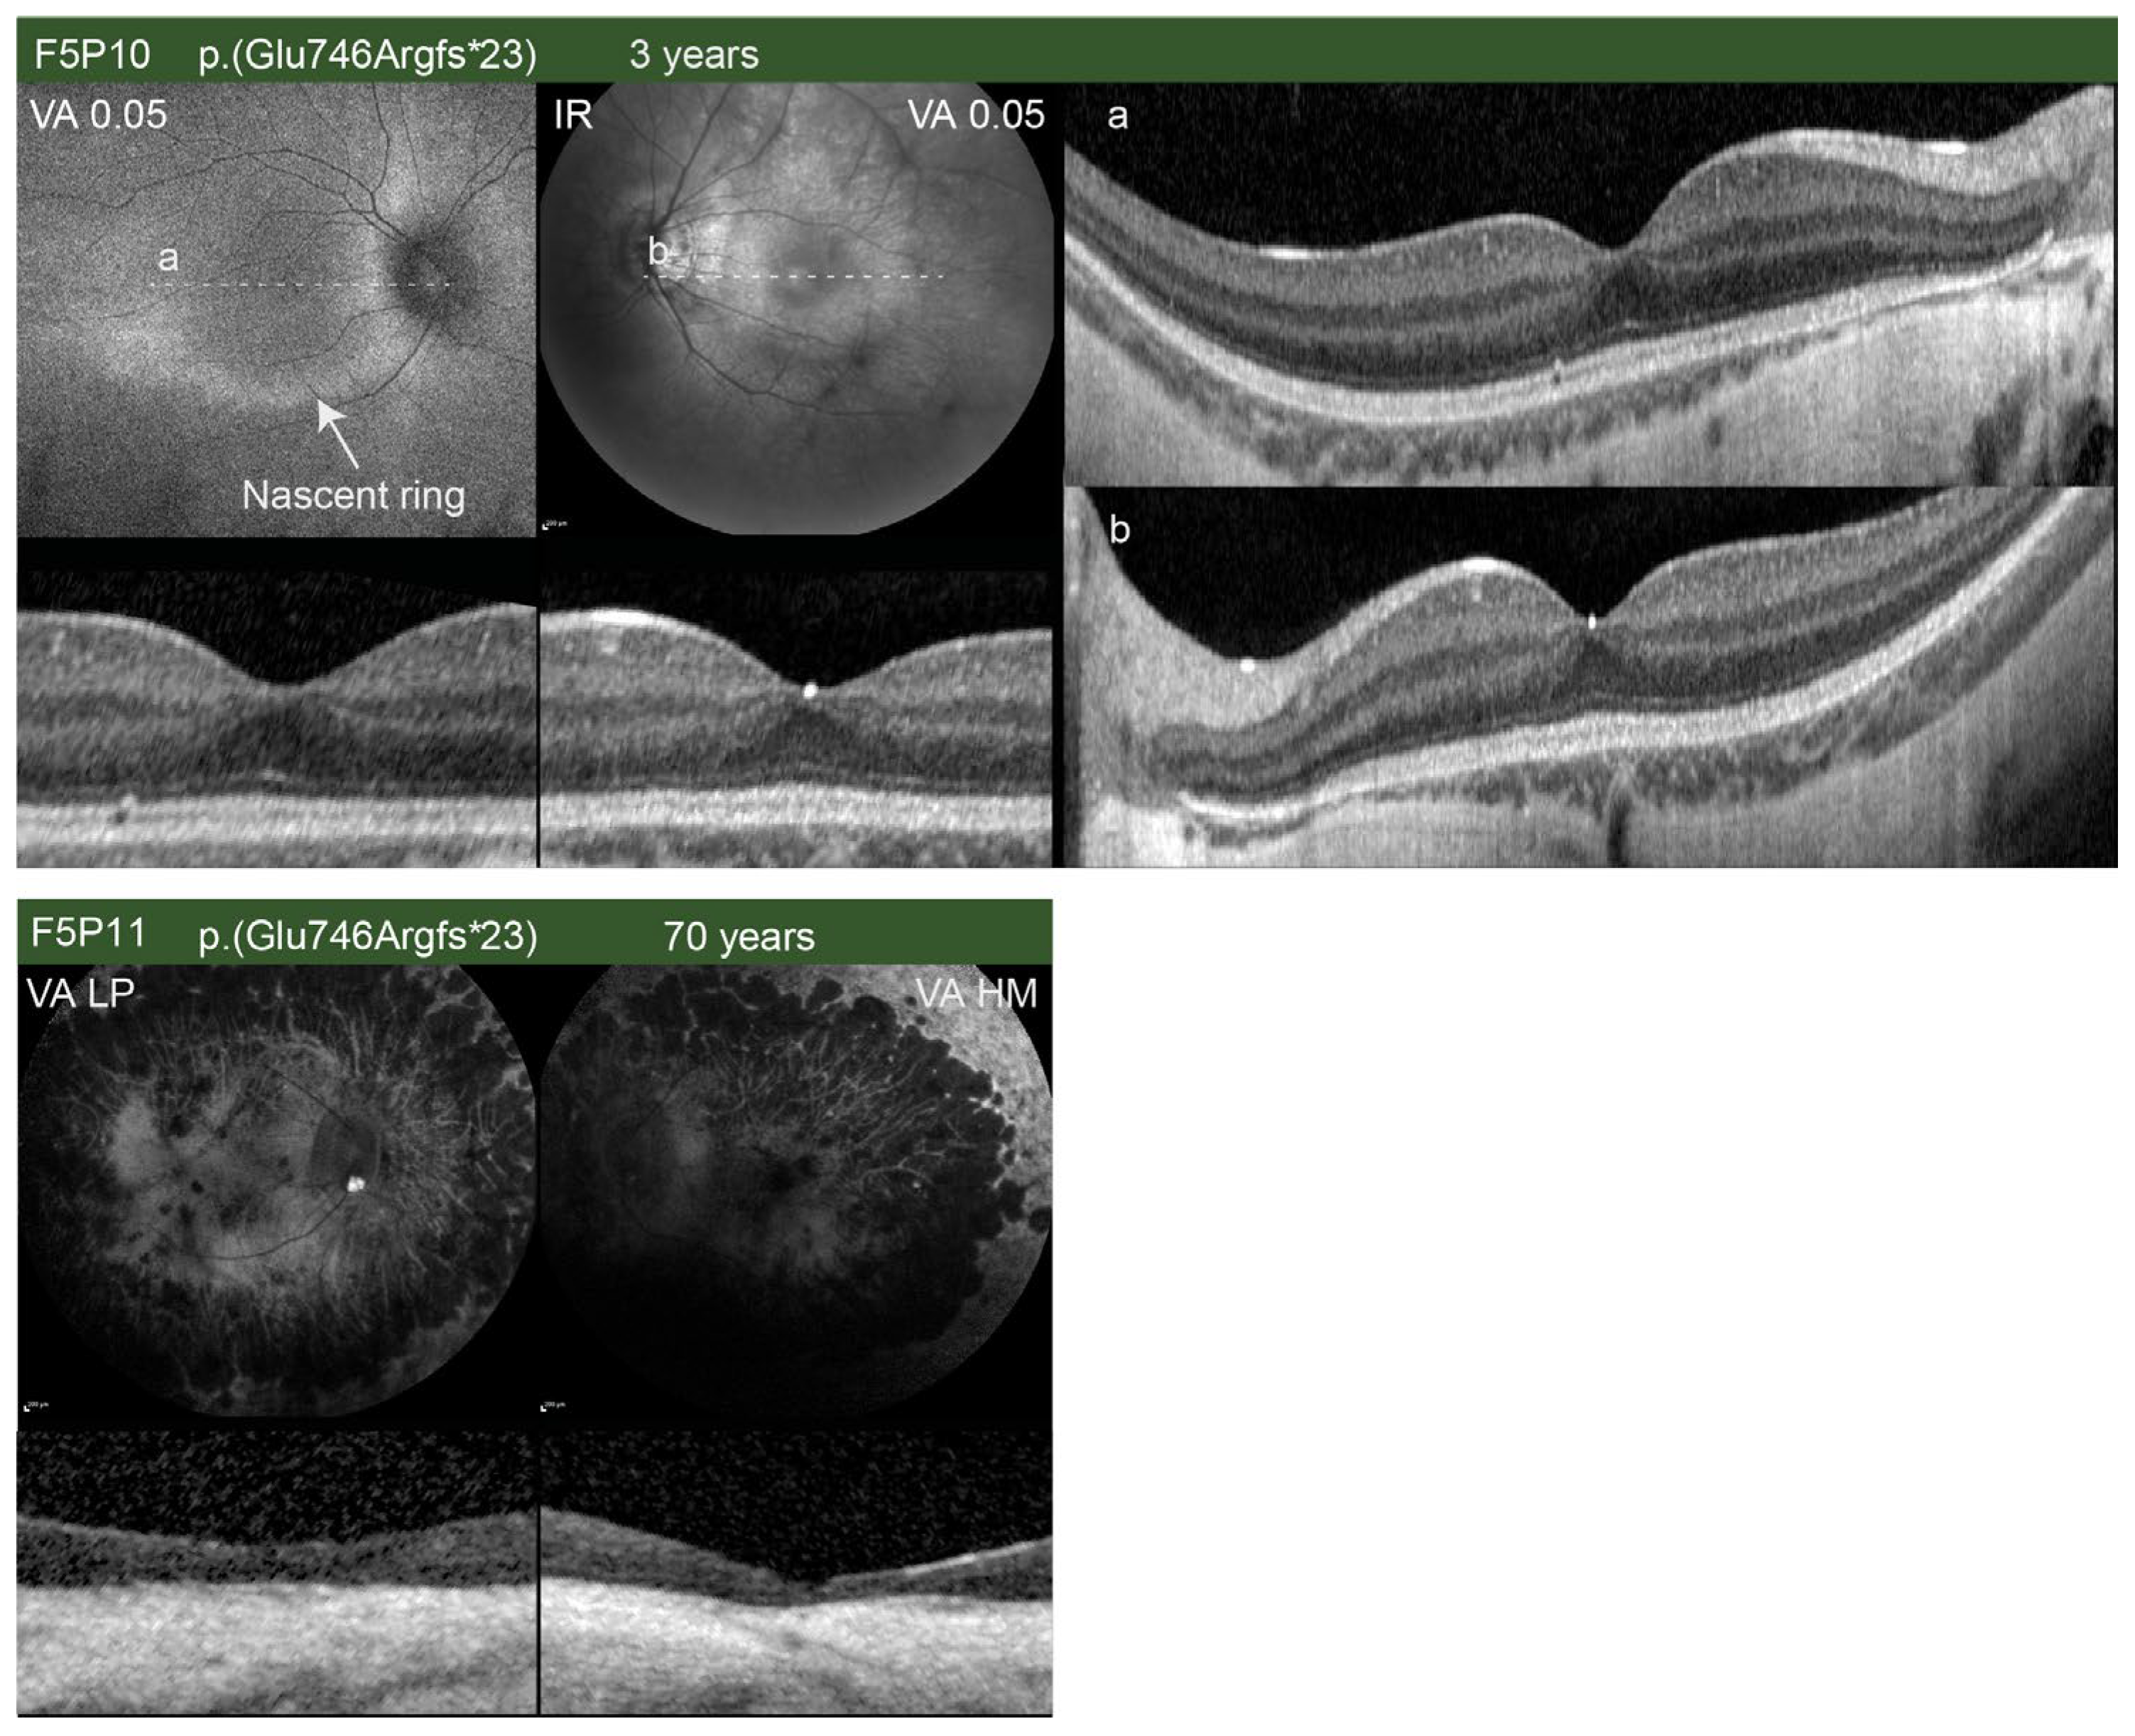

| F5P10 (00380) | M | RP | c.2236_2237delGA p.(Glu746Argfs*23) | Yes [22]) | Less than a year (11 months); 3 | Childhood | N/A | N/A (−9.0) | N/A (−10.0) | 6/130 (0.2); 6/24 (0.60) | 6/130 (0.30); 6/18 (0.47) | N/A | BE: Slight peripapillary atrophy, dystrophic retina | N/A | N/A | N/A | N/A | N/A | N/A | BE: Normal DA ERG; slightly reduced LA ERG |

| F5P11 (01054) | M | RP | c.2236_2237delGA p.(Glu746Argfs*23) | Yes [22] | 61; 70 | N/A | N/A | −11.0–4.50/15° (N/A) | −9.0–4.0/17° (N/A) | 0.01 (2.3); hand movement | 0.005 (2); hand movement | N/A | BE: Optic pallor, attenuated vessels, degenerative changes | N/A | BE: Absent RPE, Ise, and ELM in the central macula | N/A | N/A | N/A | N/A | BE: Undetectable LA and DA ERG |